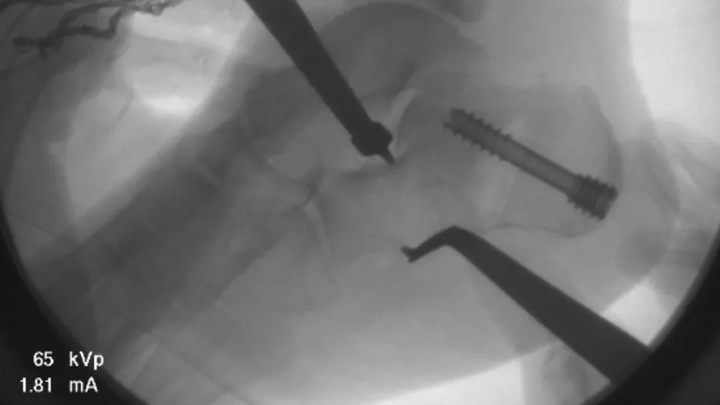

Hailey’s surgery went well, and we are incredibly thankful for all the love, prayers, and support we've received.